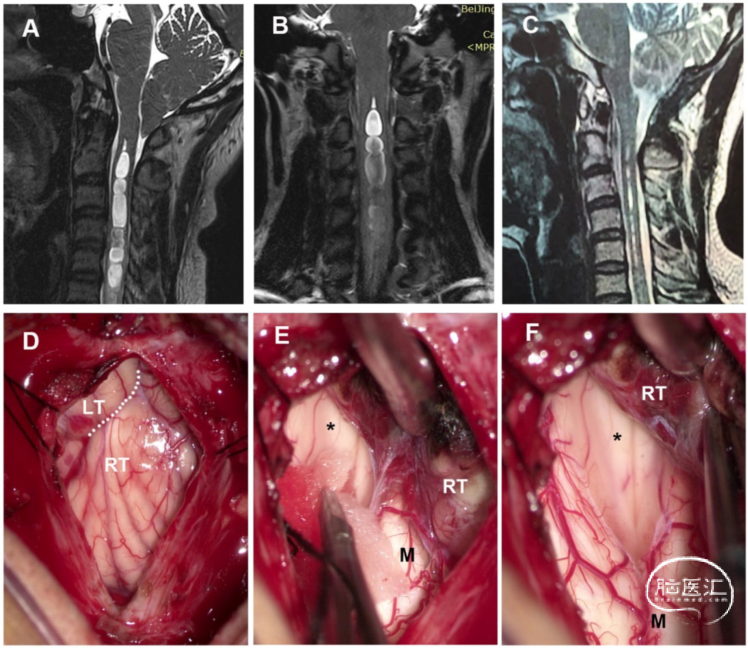

男性,68岁,有10年的双上肢麻木和无力病史。术前MRI显示颈胸段SM伴第四脑室扩张。硬膜内手术显示,扁桃体下坠到延髓蛛网膜粘连(星号)并覆盖在Magendie孔上。分离和切除部分粘连蛛网膜。术后MRI显示,SM的大小显著减小。术后症状部分缓解(图2)。

图2. 经典交通型CM-SM病例。A. 术前MRI-T2加权矢状位成像。第四脑室扩张和SM(星号),第四脑室与SM之间的通道(黑色箭头)。B. 术后MRI显示,SM明显减少。C. 扁桃体分离显示扁桃体到延髓蛛网膜粘连(星号)覆盖在Magendie孔上。D. 松解蛛网膜粘连和暴露的Magendie孔(箭头)。LT:左扁桃体;M:延髓;RT:右扁桃体。